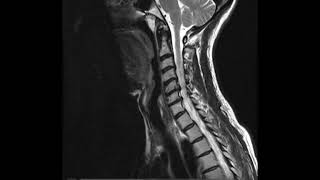

Hola mis amigos cómo andan vamos a ver la parte número dos de columna lo que hace a columna cervical vemos que esta columna cervical está formada por siete vértebras que se enumeran primero segunda tercera cuarta quinta sexta y séptima que tienen particularidades la primera y la segunda tienen particularidades diferentes al resto la primera se llama Atlas va a articular con el occipital es por eso se llama Atlas Atlas era el dios griego que sostenía el mundo y la segunda se llama axis Atlas la primera axis la segunda 3 4 5 6 y 7 no tienen

nombre salvo la séptima que por tener una pisis Espinosa mucho más saliente y voluminosa se llama vértebra prominente Entonces si les preguntamos Cuál es la vértebra prominente es la séptima vértebra cervical una vértebra cervical tipo presenta estas características un un cuerpo que es rectangular con su diámetro transverso mayor las apófisis transversas que nacen de dos patitas de dos porciones o raíces y delimitan el agujero transversal por donde va a pasar la arteria y vena vertebral salvo en El séptimo la séptima vértebra cervical carece de contenido el agujero transversal después vemos el pedículo las láminas y

la apis Espinosa que es bitu bercula la segunda la tercera la cuarta La Quinta y la sexta tienen apófisis espinosas bitu bercula la séptima no la séptima es prominente y tiene un solo tubérculo entonces este es el Atlas y este es el axis que son dos vértebras diferentes al resto el Atlas no tiene cuerpo está formada por las masas laterales que tienen cada una de ellas una cavidad glenoidea que es esta que va corresponder al cóndilo del occipital un arco anterior y un arco posterior de las masas laterales sale la apsis transversa muy chiquitita con

su agujero transversal por donde también pasa la arteria y vena vertebral en la parte en la cara interna de las masas laterales en la unión del tercio medio con el tercio externo a este nivel Acá hay un ligamento que se llama ligamento transverso que va a dividir al conducto que tiene en el medio el Atlas en dos segmentos uno anterior articular que va a recibir a la apófisis odontoides que acá se ve perfecto y uno posterior que va a corresponder al conducto raquídeo o medular el axis tiene un cuerpo cuadrilátero dos cadillas articulares para el

atras hacia arriba y después no tiene ninguna particularidad salvo este elemento cilíndrico esta apófisis que es la apófisis odontoides típica qué vértebra es la dueña de la apófisis odontoides eraxis esta apó odontoides se va a introducir por detrás del Arco anterior en el compartimento articular del Atlas y va a formar una articulación que es la atloidea odontoidea que es una trocoides características generales el cuerpo el pedículo la apis transversa que tiene en su interior el agujero transversal acá vemos las láminas y la apicis Espinosa que es bit tuberculosa estas son superficies articulares para las este

todas las vértebras cervicales entre sí Y otra característica que acá no está muy bien marcado pero la cara superior del cuerpo de las vértebras cervicales a este nivel hay unas apófisis en forma de gancho o de semiluna que se llaman apófisis semilunares están solamente a nivel de las vértebras cervicales y forman lo que se denomina uncoartrosis la articulación de una apófisis semilunar con las de arriba con la de abajo se llama uncoartrosis la uncoartrosis es típica de las vértebras cervicales apoyes articulares el Atlas con su masa lateral las cabas glenoideas para que articule con los

cóndilos de occipital el arco anterior el arco posterior la apis transversa y el ligamento transverso Esta es la parte articular y esta es la parte nerviosa acá vemos el axis con el cuerpo y la apófisis odontoides vista de atrás y acá vemos como articulan el Atlas con el axis en un coito continuo Acá hay una cosa una relación medio rara y ahí vemos el ligamento transverso que cierra por detrás el compartimento articular de bueno no hay más para decir de las vtas cervicales éxito gente nos vemos pronto Hasta lueguito